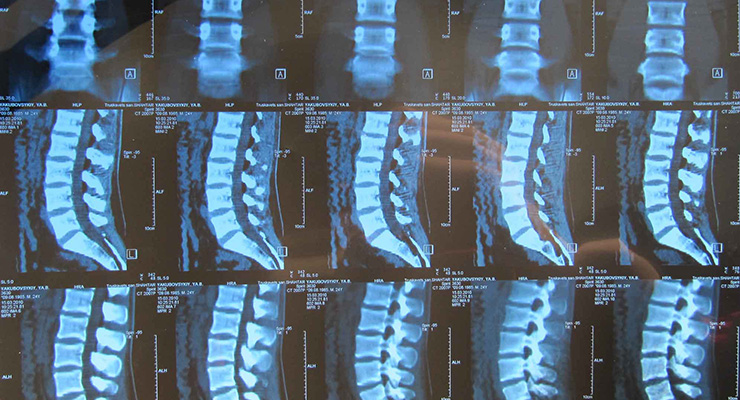

Диагностика спондилеза

Для постановки точного диагноза заболевания позвоночника необходимо провести комплексное лечение с помощью специального медицинского оборудования. Наиболее информативный способ обследования , МРТ и компьютерная томография. Врач может назначить оба обследования или выбрать один из методов. Они позволяют выявить поврежденный участок позвоночника, определить расположение и размеры отростков. Рентгенография позвоночника дает информацию о локализации, обширности и стадии поражения.

Важным диагностическим этапом является определение площади патологии и характера костных образований. При спондилезе затронуто 1-3 позвонка, выражено окостенение, наросты имеют неправильную форму, могут быть направлены вверх, вниз, срастаться по принципу «,клюва попугая», и даже окольцовывать позвонок.

При остеохондрозе наросты расположены перпендикулярно позвоночнику, нет тенденции к сращиванию. Болезнь Форестье затрагивает больший участок с деформацией более 3 позвонков.